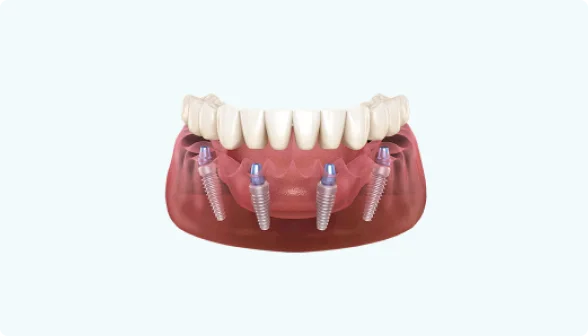

Так будет выглядеть конструкция на нижней челюсти.

В конструкцию на 4-х имплантах входит:

- 4 Импланта

- 8 Коронок

Импланты устанавливаются в области 5-го зуба под углом, что позволяет избежать дорогостоящей операции по наращиванию костной ткани.

Для того, чтобы была возможность использовать винтовой тип фиксации коронок к абатменту, имплант должен быть установлен не под углом, как это делается в методе на 4-х имплантах.

Метод протезирования на 4-х имплантах более доступный по цене, чем метод ALL ON 6

Экономия достигается за счёт того, что вместо 6 имплантов, ставятся 4 импланта и за счёт того, что импланты ставятся под углом, чтобы обойти гайморову пазуху (если мы говорим про верхнюю челюсть) или чтобы не попасть в мандибулярный нерв (если мы говорим про нижнюю челюсть).